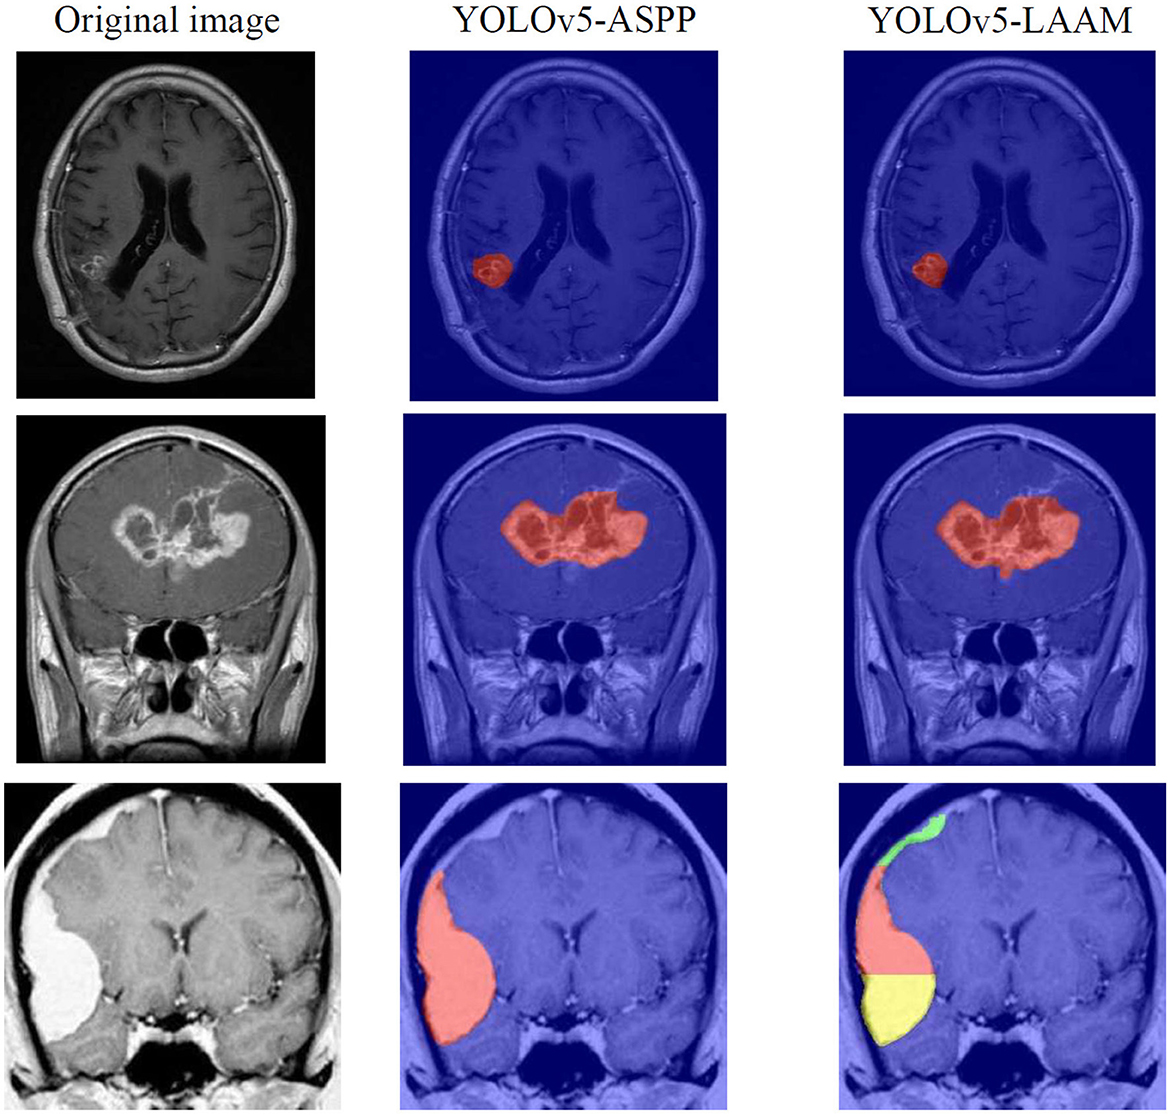

As shown in Tables 7, 8, on the internal test set, YOLOv5s-LAAM outperformed YOLOv5s-ASPP in both overall performance (mAP@50: 0.833) and recall rate (0.824), compared to the latter's scores (0.826 and 0.784, respectively). This indicates its superior lesion coverage capability and improved control over missed detections. Although its precision (0.748) on the external test set was lower than that of the ASPP variant (0.82), LAAM still maintained a higher recall rate (0.741). Furthermore, as illustrated in Figures 9, 10, it provided more complete and accurate localization and delineation of tumor regions.

Figure 9

Test results of YOLOv5-ASPP and YOLOv5-LAAM on the internal test set.

Figure 10

Test results of YOLOv5-ASPP and YOLOv5-LAAM on the external test set.